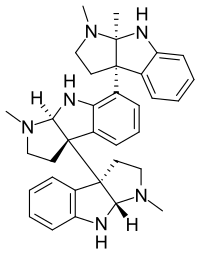

There are a number of broad classes of opioids:[260]

- Endogenous opioid peptides, produced naturally in the body, such as endorphins, enkephalins, dynorphins, and endomorphins.

Opium alkaloids and derivatives